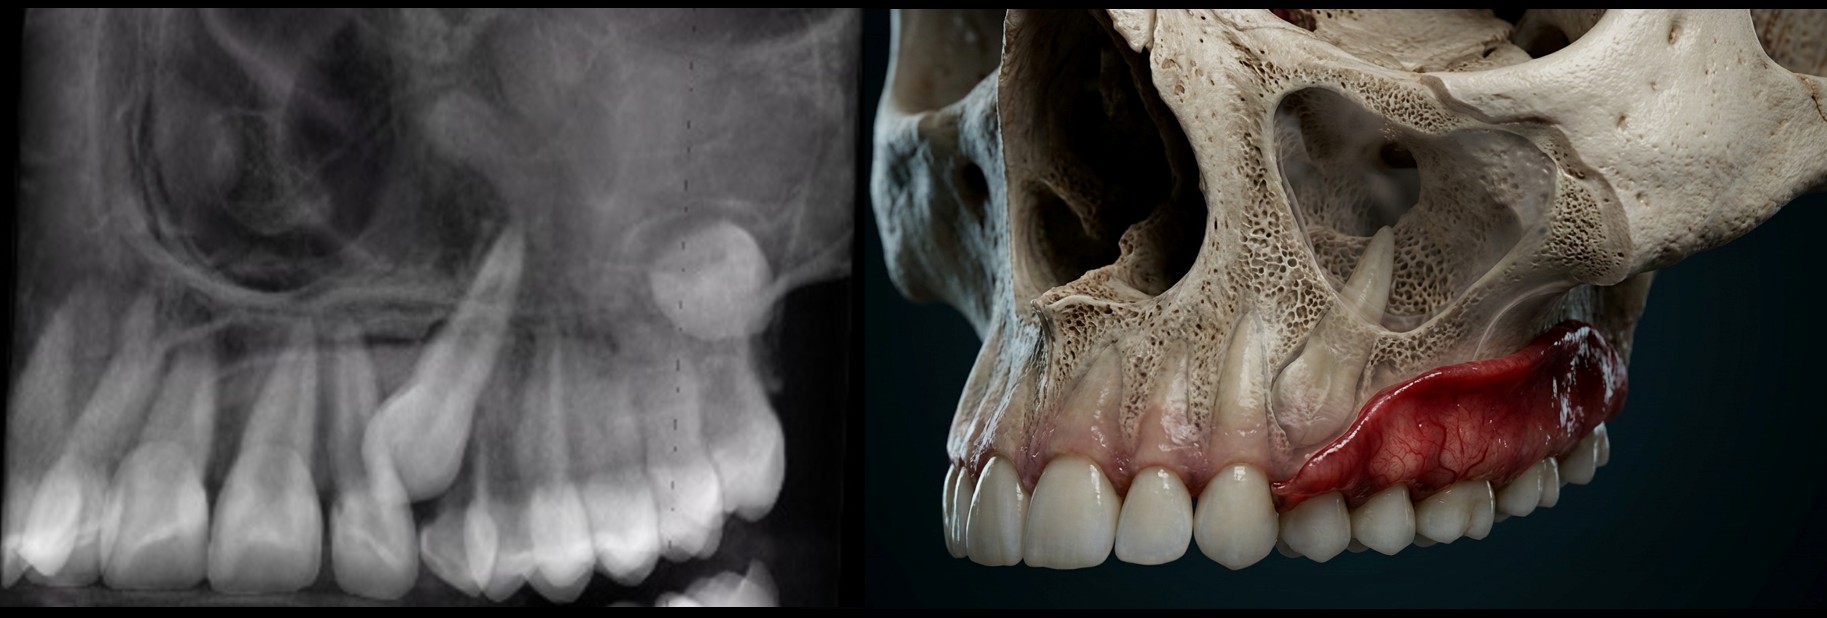

What if I told you that in just two days you could learn a repeatable, radiologist-level workflow to confidently diagnose vertical root fractures, recognize extra-radicular infections, and interpret advanced CBCT findings that many clinicians miss—especially when artifacts make the scan “look unreadable”? Now imagine doing that in beautiful Santa Barbara, California. Picture reviewing a CBCT scan like the one below—streaking, scatter, motion, and metal artifacts obscuring the details that matter most. Instead of guessing, you’ll know exactly what to look for, how to use MAR vs. BAR filtering appropriately, and how to make a confident call when the findings are subtle. By the end of this hands-on course, you’ll be able to read challenging cases with clarity, improve clinical decision-making, and communicate your findings more effectively to your team and referring doctors.

Master Vertical Root Fracture Diagnosis

Learn the techniques that will allow you to confidently identify fractures—even in cases where artifacts make it nearly impossible for others.

Spot Extra-radicular Infections with Precision

Gain the skills to detect and differentiate infections that could otherwise be missed.